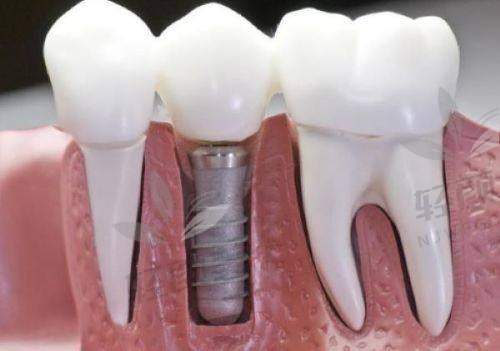

黎强医生真的特别亲切,他详细地询问了我的牙齿情况和病史,然后带我去做了全方面的口腔检查。检查设备都特别精良,整个过程也特别舒服。检查完之后,黎强医生给我分析了我的牙齿状况,耐心地给我讲解了穿颧穿翼种植牙的原理和过程。他说我的牙槽骨条件不太好,普通种植牙可能成效不佳,而穿颧穿翼种植牙可以利用颧骨和翼板的骨质,为种植体提供更稳定的支撑。我听了之后,心里踏实了不少。

黎强医生根据我的检查结果,为我制定了个性化的穿颧穿翼种植牙方案。他给我看了特别多类似实例的前后对比照片,让我对手术成效有了更直观的认识。我对方案特别满意,但是心里还是有点担心手术的风险和疼痛。黎强医生看出了我的顾虑,他安慰我说,穿颧穿翼种植牙技术已经特别成熟了,他做过特别多这样的手术,成功几率非常高。而且手术过程中会使用精良的麻醉技术,不会让我感觉到疼痛。听了他的话,我心里的石头终于落了地。